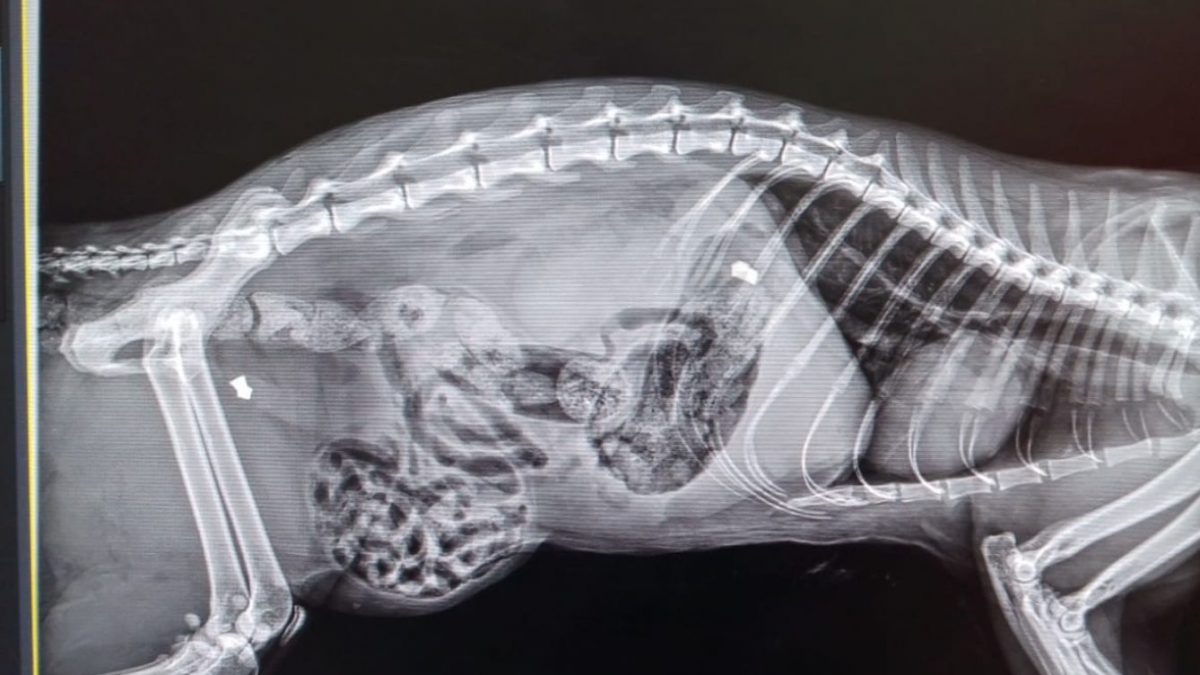

Alla veterinaria che lo aveva preso in carico, la ferita però non era sembrata un trauma da scontro: «Per nulla convinta di quella spiegazione, la dottoressa ha deciso di fare una lastra dalla quale ha purtroppo constatato che la causa delle ferite mortali era riconducibile a due colpi di fucile sparati da distanza ravvicinata. Non c'è dubbio sul fatto che si sia trattato di un'azione intenzionale che non ha lasciato nessuno scampo all’animale».

Il micio era in buona forma e ben curato, non sembrava affatto un gatto randagio e proprio per questo i volontari non hanno escluso che potesse avere una famiglia che lo aspettava. «Speravamo di trovare il suo umano. Per questo abbiamo postato la foto della radiografia per vedere se con un po’ di passaparola, arrivasse qualcuno a reclamarlo. Ma purtroppo niente. A quel punto, quindi abbiamo deciso di fare denuncia noi come Associazione».